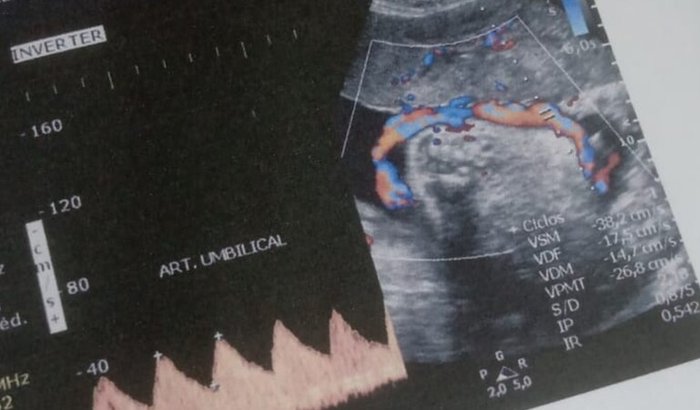

Estamos passando por um momento muito delicado. Nosso bebê, o pequeno João, ainda está na barriga, mas já enfrenta uma grande luta pela vida. Durante os exames recentes, descobrimos que ele está com o cordão umbilical enrolado no pescoço — uma condição que coloca sua vida em risco e exige cuidados médicos urgentes e especiais.